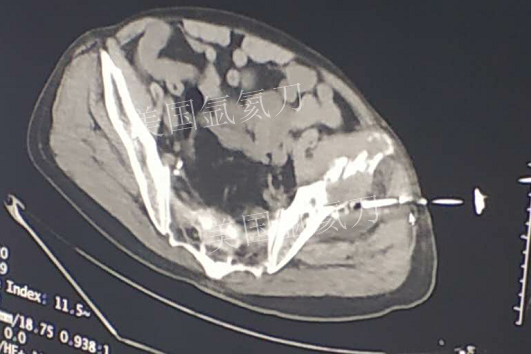

73岁臀部氩氦刀冷冻消融

发布人:美国氩氦刀技术官方网站    发布时间:2019/2/21 13:51:52